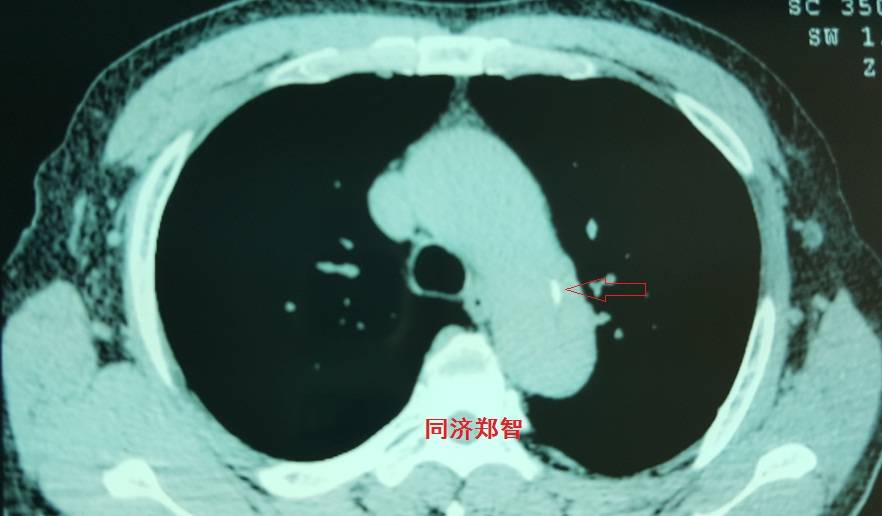

病例六

平扫CT提示降主动脉内膜片影(白箭头所示),CTA显示为B型主动脉夹层。